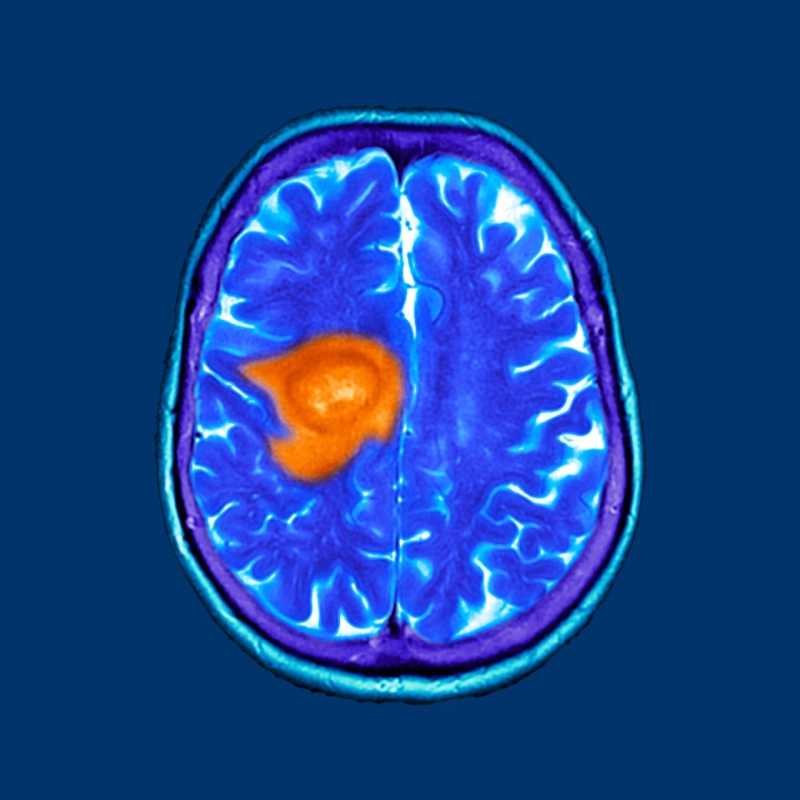

- Many tumors exist in low-oxygen environments, known as hypoxia. This condition can make them more resistant to radiation therapy and certain chemotherapies. HBOT may increase oxygen delivery to these areas, potentially making cancer cells more vulnerable to treatment.